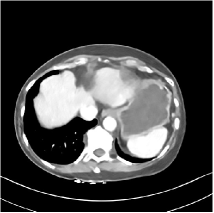

Fig. 3: Three examples (from top to bottom) of the reconstructed testing images using Momentum-Net with SimpleCNN (the second column), with SimpleCNN-RSN (the third column), and with Dn-RSN (the fourth column). The compared WavResNet denoised images are shown in the first column, and the reference images are in the fifth column. See their FBP images in Fig. 4.

Refer to caption

Fig. 4: FBP images of test examples.

Fig. 2 shows that the proposed Momentum-Net with SimpleCNN decreases RMSE dramatically in the first 30 layers, and tends to converge in 50 layers. The Momentum-Net reduces the mean RMSE value by 4.5 HU and gives smaller standard deviations in RMSE, compared to WavResNet, as reported in Table 1. This implies that the proposed Momentum-Net with SimpleCNN can improve both the accuracy and stability of low-dose CT image reconstruction than a state-of-the-art image denoising deep NN, WavResNet. The proposed Momentum-Net with SimpleCNN better removes noise and streak artifacts than WavResNet. It also provides clearer reconstructions of some details; see, in Fig. 3, the boundaries shown in the zoomed region at the top-right corner in the first example, the arrow pointed structures in zoomed areas of the second example, and the arrow pointed tissues in the left zoomed region in the third example.

3.3 Momentum-Nets involving RSN-based training

We show the reconstructed examples by Momentum-Net with SimpleCNN-RSN and Dn-RSN in the third and fourth columns of Fig. 3 respectively. Comparing the first three and the last columns in Fig. 3, we observe that Momentum-Net with SimpleCNN-RSN provides generally noisier reconstructions than WavResNet and Momentum-Net with SimpleCNN. However, Momentum-Net with SimpleCNN-RSN sometimes can provide clearer details than WavResNet. For example, in the right zoomed box of the second example, Momentum-Net with SimpleCNN-RSN shows better reconstruction quality for the arrow pointed structures than WavResNet, and in the left zoomed box in the third row, the former gives clearer small tissues marked by red arrows than the latter. Table 1 reports that Momentum-Net with SimpleCNN-RSN is approximately 2.9 RMSE (HU) higher than WavResNet, while it has smaller standard deviations. This implies that Momentum-Net with SimpleCNN-RSN is more stable than WavResNet, although it may not provide better image qualities. Momentum-Net with Dn-RSN, however, provides the worst visual and numerical results among the compared four methods in this paper.